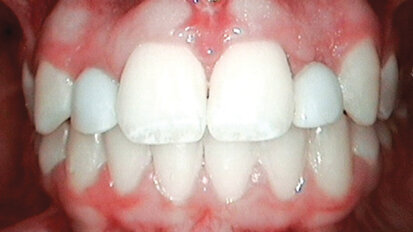

Let patients test-drive their new smiles

The decision to pursue ceramic dental restorations is a major one for most patients. There may be a concern that the results will turn out to be different ...